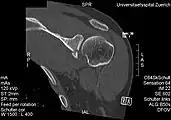

- CT scan showing a bony Bankart lesion at the antero-inferior glenoid